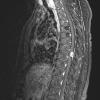

NEOPLASMS (MENINGIOMA)

Transitional (4)